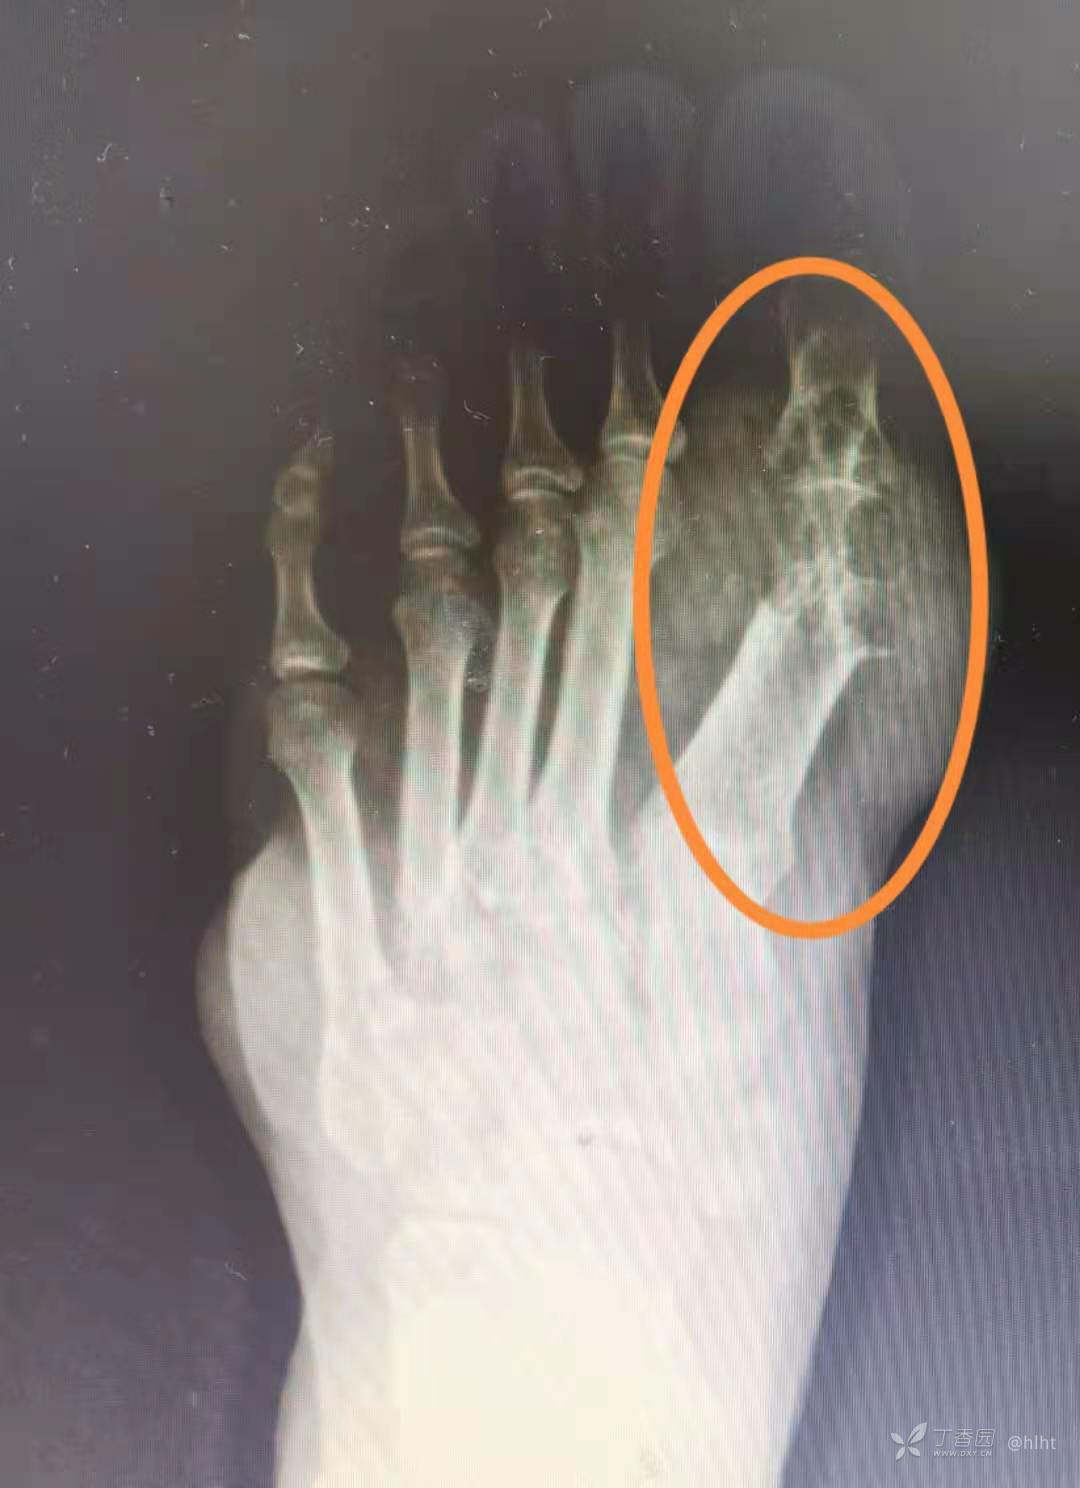

男性,25岁,3月前外院行左足第一足趾跖关节处痛风石切除术

X片

25岁,这么严重的痛风,还是第一次遇到;